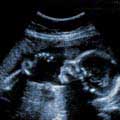

Бремени сте: 20 недели

Честитаме, ја преживеавте првата половина од бременоста. Доаѓа период на брзо растење на матката, затоа стомакот видливо се напнува. Плодот ја притиска бешиката, па често мокрите. Некои трудници малку потешко дишат, бидејќи внатрешните органи, пред се желудникот, поради растењето на матката ги притискаат белите дробови. Оваа недела на ред е ултразвучен преглед кој се вика морфологија. Испитувањето е многу важно, бидејќи гинекологот детално го прегледува плодот и дава конечно мислење за развојот.

Плод во 20. недела

Плодот е сега приближно голем 25 см, а тежок околу 300 грама. Освен коса, сега почнуваат да растат веѓите и трепките. Целото тело и лице е прекриено со нежни влакненца кои кај повеќето бебиња паѓаат пред нивното раѓање. На девојчињата оваа недела почнува да им се развива матката, а потоа на ред доаѓа и вагиналниот канал. <